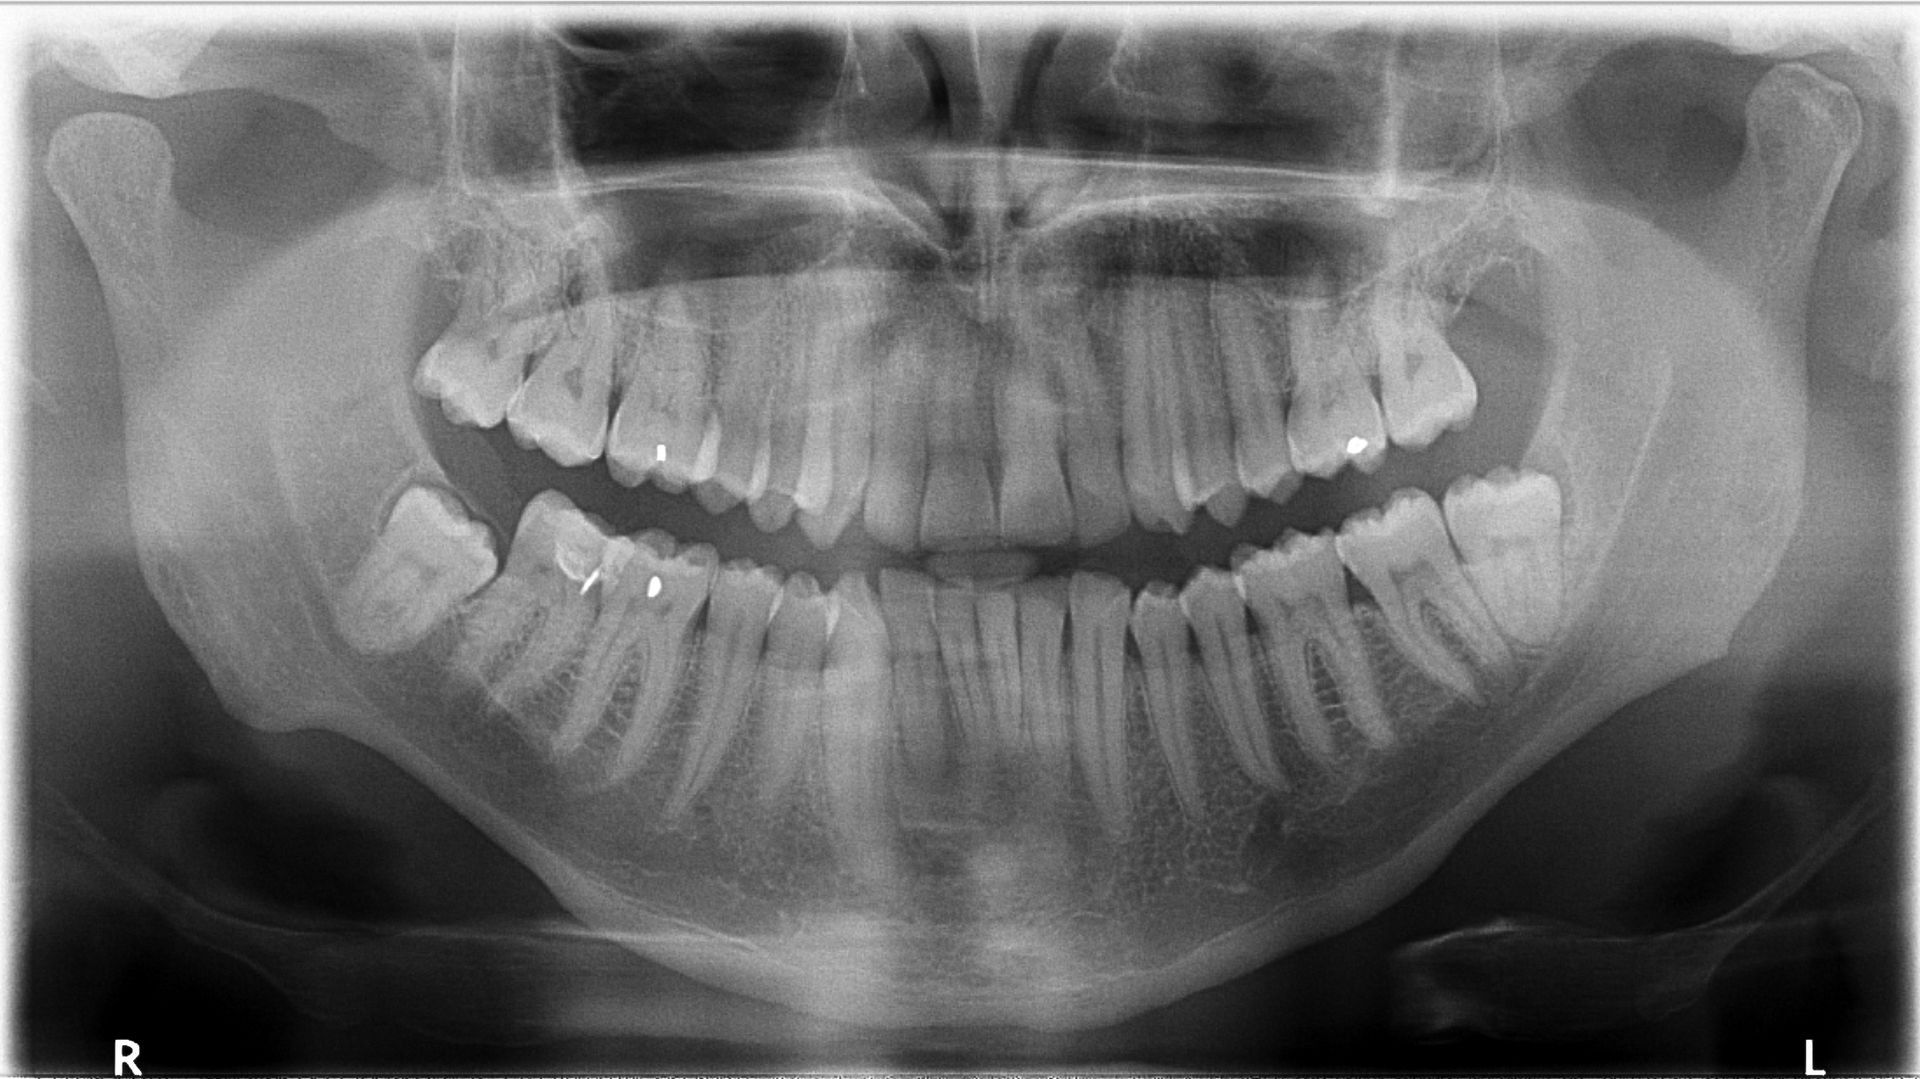

Clear, Comprehensive Imaging With Panoramic Digital Radiographs

Why Choose Panoramic Digital X-Rays?

- Low radiation—safer than traditional imaging (up to 80% less)

- Fast, comfortable, and non-invasive

- No chemical processing

- Captures the entire mouth in one image

- Helps detect impacted teeth, jaw issues, infections, and more

- Better patient understanding—you can view the image with us during your visit

Whether you're having your wisdom teeth assessed, preparing for orthodontics, or needing a thorough check-up, panoramic radiographs help us provide clearer insights and more precise care.